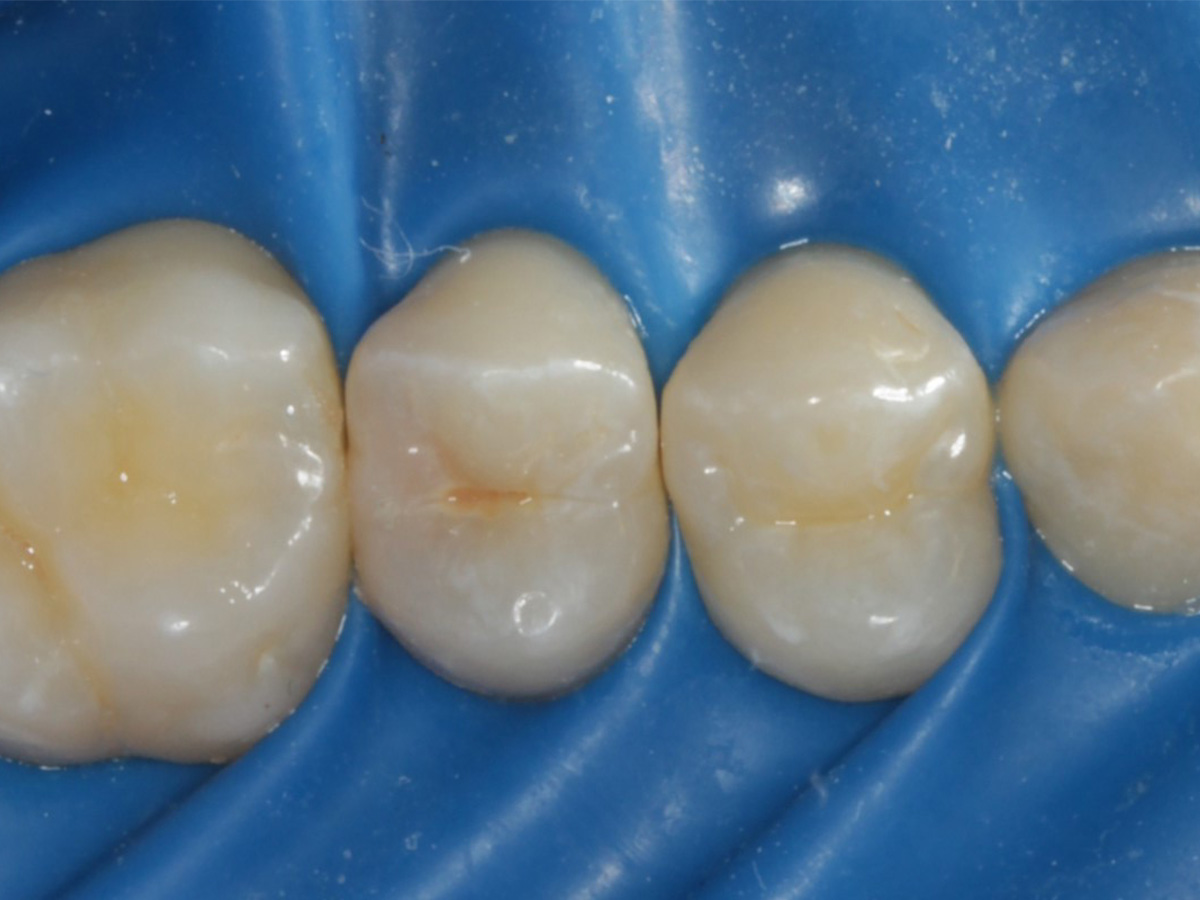

Abbildung 28

Kompositrestauration nach „Schachtverschluß“; keine Krone geplant